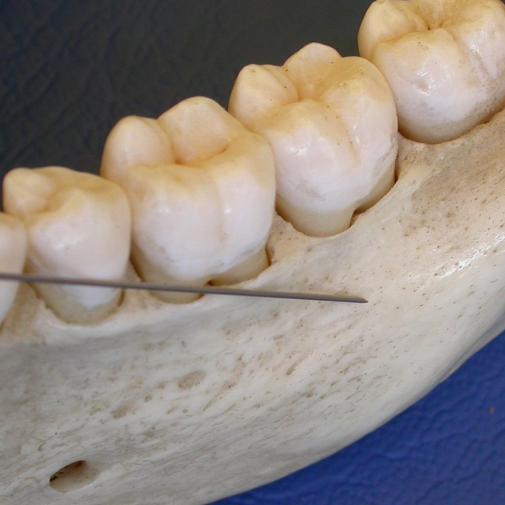

Je krijgt inzicht in het handinstrumentarium; welke instrumenten passen bij een behandeling? Het verschil tussen de standaard gracey curette, de after five curette en de mini five gracey curette wordt doorgenomen. Ook bespreken we 15/16, 17/18 curettes, NEVi scalers en Diamondtec furcatie files.

Tevens behandelen we de invloed van retentiefactoren, het slijpen van instrumenten en de handvaardigheid. Ook bieden wij je een verdieping in de techniek van de scaler en curettes, toegepast in verschillende werkgebieden.

• Kan instrumenten uitproberen op een fantoomhoofd